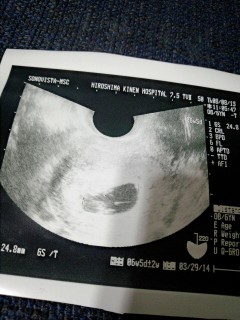

8w0dのはずでしたが、この大きさだと6w終わりから7w位だねと先生に言われました。

赤ちゃんの体長(CRL)11.4mm

心拍141/分

前回5w0dの時は胎のうが4.1mmだったので3w経って成長してる我が子を見て、心臓が動いてるのを見て嬉しく思いました。